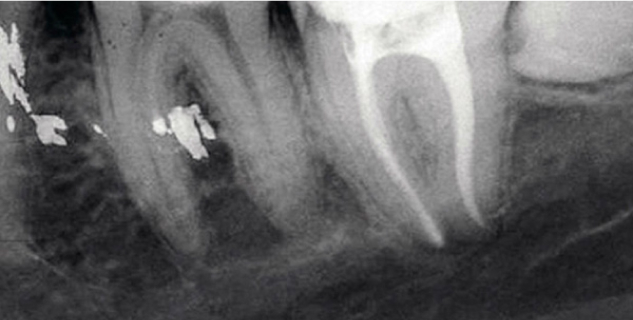

• Радиовизиограф позволяет выявить количество, длину, строение каналов, качество их прочистки, плотность заполнения пломбировочным составом.